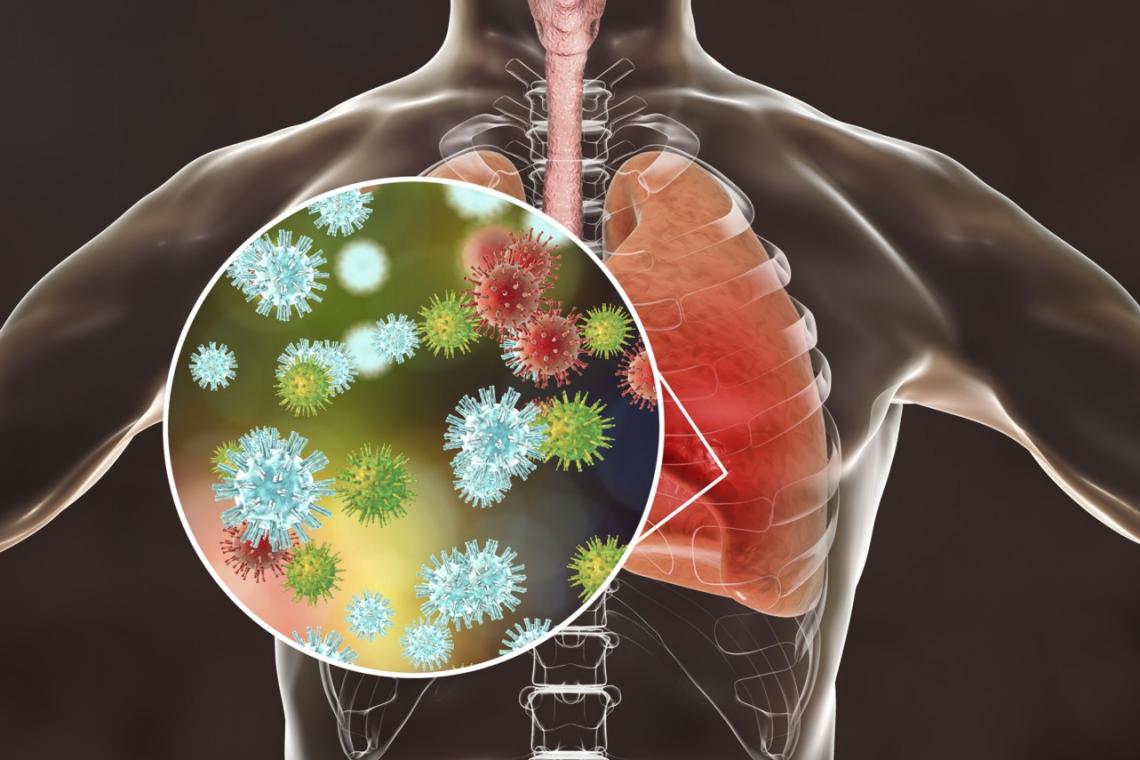

El objetivo del trabajo era averiguar qué células de los sistemas respiratorio y digestivo pueden resultar infectadas por el coronavirus SARS-CoV-2, por lo que los científicos buscaron qué células expresan al mismo tiempo la proteína ACE2 y la proteína TMPRSS2, descubriendo que sólo una pequeña proporción de células respiratorias o digestivas pueden resultar infectadas.

En los pulmones son vulnerables los neumocitos tipo II, que se encuentran en los alvéolos, las estructuras más profundas de los pulmones.